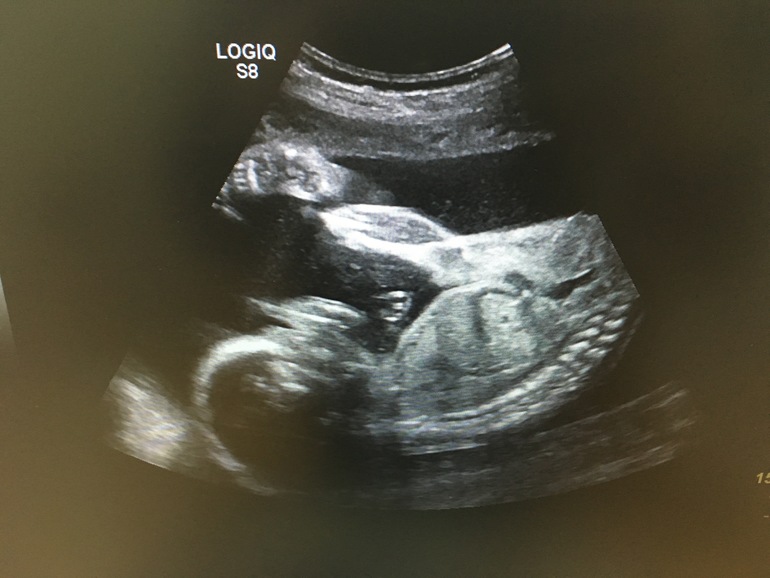

Девчонка наша развивается шикарно, опережает сроки на неделю вперед) Весит уже целых 606 грамм, зевает, чавкает и закидывает ножки к голове! По допплеру посмотрели мои артерии и пуповину - все хорошо, ох, люблю я свою матку)))))

Фотки с УЗИ и вопросы про выбор коляски под катом, вэлкам)

И ниже обещанные фотки с УЗИ) Есть еще видео, но загружать сюда сложнова-то, не стала пока